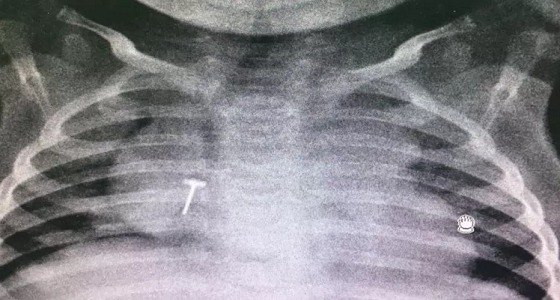

إنقاذ رضيع ابتلع جسم معدني بـ ” سعود الطبية “